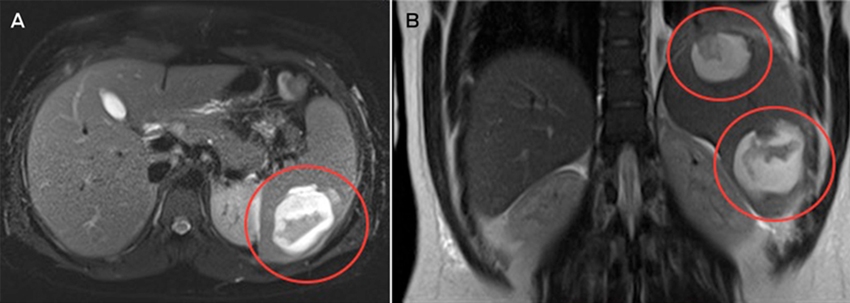

Magnetic resonance imaging of the abdomen suggested that the two splenic lesions were likely to represent abscesses in this clinical context (Figure). Given our patient’s ongoing sepsis, a decision was made to perform a laparoscopic splenectomy for source control on Day 5 of admission. Surgical specimens tested positive for Salmonella Virchow. Histopathological testing identified cystic lymphangiomas of the spleen. Despite problems with postoperative pain and a prolonged ileus, the patient made a full recovery. He received appropriate post-splenectomy vaccinations, along with a total of 2 weeks’ intravenous ampicillin, followed by a 2-week course of oral amoxicillin.